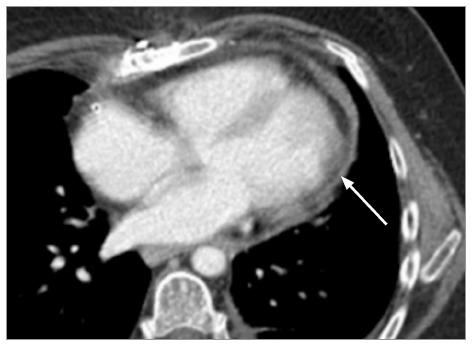

左心室游离壁破裂是心肌梗死的致命并发症。尽管紧急手术修复是首选治疗方法,但修复方法仍高度个性化。本报告介绍了一例特纳综合征患者自发性冠状动脉夹层导致左心室游离壁破裂的病例,该患者在心肺旁路手术中使用 EVARREST 纤维蛋白密封补片无缝合技术成功修复了左心室游离壁。

Left ventricular free wall rupture is a lethal complication of myocardial infarction. Although emergent surgical repair is the treatment of choice, the method of repair remains highly individualized. This report presents a case of spontaneous coronary artery dissection in a patient with Turner syndrome that led to left ventricular free wall rupture and was successfully repaired on cardiopulmonary bypass using a suture-free technique with the EVARREST Fibrin Sealant Patch.